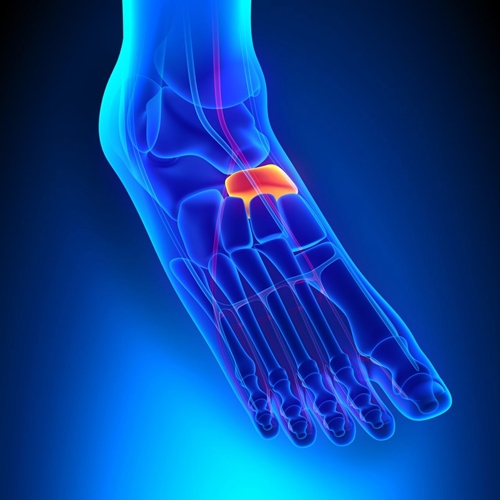

주상골(navicular bone)은 발목뼈(족근골)(tarsal bone)를 구성하는 뼈(bone) 중 하나입니다. 위치상으로 살펴봤을 때 입방골(cuboid bone)과 설상골(cuneiform bone), 그리고 거골(talus) 사이에 자리 잡은 뼈(bone)입니다. 그렇다 보니 방향적인 위치상 발목 안쪽(internal ankle)으로부터 타고 내려와, 실질적으로 발의 아치(foot arch)가 가장 높게 실리게 되는 위치상에 존재하게 됩니다. 주상골(navicular bone)의 자세한 모습과 위치는 사진을 통해서 제대로 살펴볼 수 있습니다.

사진에서 살펴본 것과 같이 주상골(navicular bone)은 단일한 뼈(bone)입니다. 하지만 부주상골증후군(accessory navicular syndrome)은 주상골(navicular bone)이 하나가 아닌 증상과도 같습니다. 그래서 그 이외의 뼈(bone)를 부주상골(accessory navicular bone)이라 부릅니다. 기본적으로 부주상골(accessory navicular bone)은 더 작은 크기(small size)로 형성되어있으며, 그 위치는 부주상골(accessory navicular bone)이라는 이름답게 주상골(navicular bone) 옆(lateral)에 자리 잡게 됩니다.